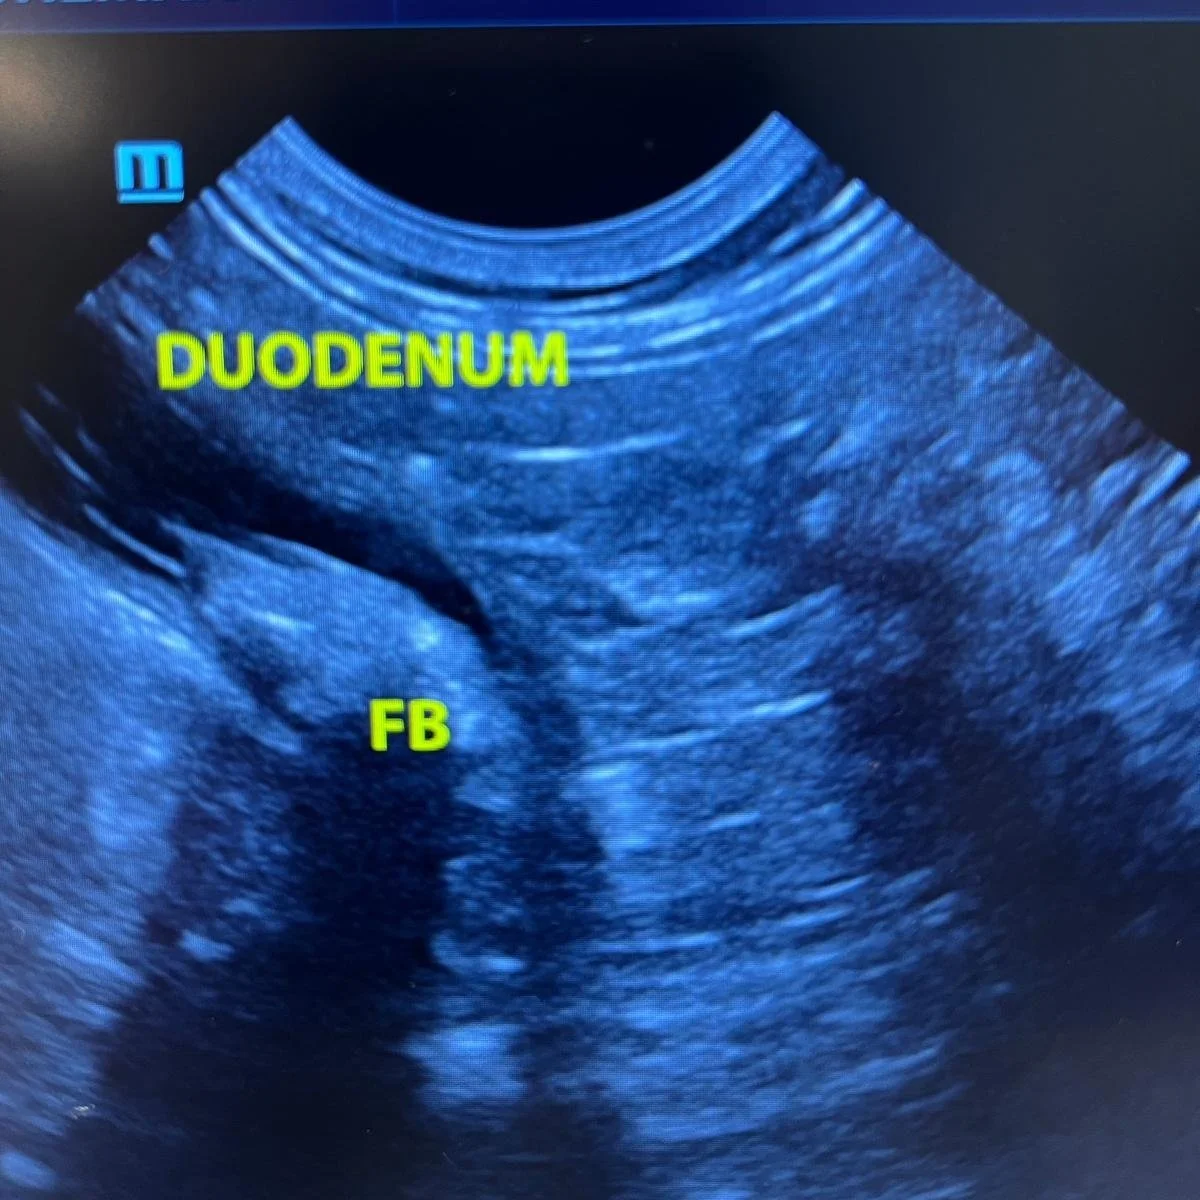

During a veterinary ultrasound, we use a small handheld probe that glides smoothly over your pet's fur and skin. The probe emits sound waves that bounce off internal organs, allowing us to create live, detailed images of your pet's internal structures on a monitor. This allows us to examine the abdomen, heart, or other areas with precision, capturing important information without causing any discomfort to your pet.